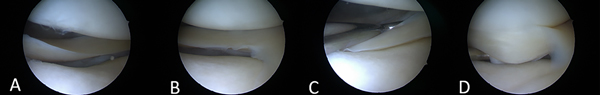

Ante la sospecha clínica, el diagnóstico definitivo se realizó artroscópicamente al evidenciar, mediante el uso del palpador, la traslación anterior excesiva del tercio posterior y cuerpo del menisco externo debido a la ampliación del ojal del poplíteo, o a la lesión de los elementos estabilizadores meniscocapsulares (fig. 1).

Figura 1: Rodilla izquierda. A-B) Visión artroscópica del menisco externo. C) Exploración sistemática del menisco externo con palpador en su cara femoral. D) Exploración de la cara tibial, se constata inestabilidad y subluxación hacia anterior.